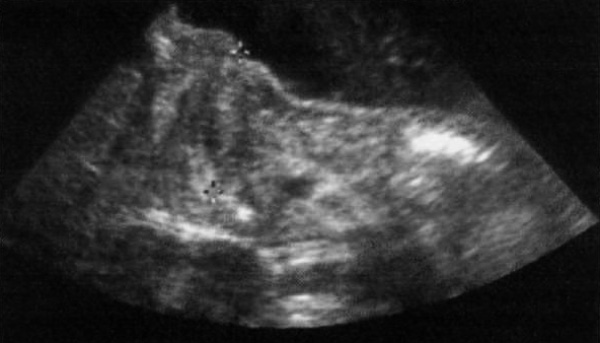

Желудок, который находится в верхнем левом квадранте живота, как правило, наполнен жидкостью и усилено перистальтирует. Основным ультразвуковым признаком гипертрофического стеноза привратника является увеличенный пилорический сфинктер, который часто визуализируют в верхнем правом квадранте живота. В поперечной плоскости увеличенный пилорический сфинктер визуализируется в форме «мишени»: пилорическая мышца выглядит как гипоэхогенная однородная структура, которая окружает эхогенную слизистую оболочку, расположенную по центру (фото 1).

Фото 1. Гипертрофический стеноз привратника. На продольном ультразвуковом изображении курсорами отмечен пилорический канал у больного с пилоростенозом. Параллельные гипоэхогенные линии соответствуют утолщенному мышечному слою по каждой стороне от просвета; центральные эхогенные линии соответствуют слизистой оболочке пилорического канала

Изображение в продольной плоскости демонстрирует утолщенные мышечные слои: параллельные гипоэхогенные линии, которые разделены эхогенной слизистой оболочкой.